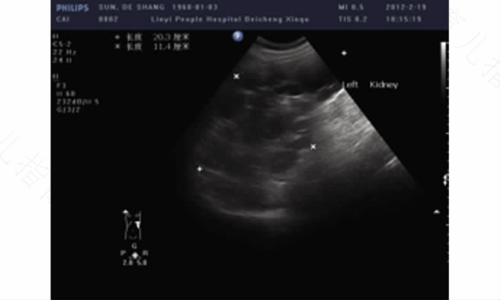

多囊肾病是一种遗传性肾病,属于先天性异常,其形成主要是由于发育异常的肾实质和结构导致,通常是双侧的,不过两侧受累程度不同。本病的主要临床症状为腰部不适或疼痛、腰部肿块、肉眼血尿、蛋白尿,易并发肾内感染。有些患者可能出现高血压,这是因为肾囊肿压迫周围肾组织,分泌过多肾素,导致肾性高血压。